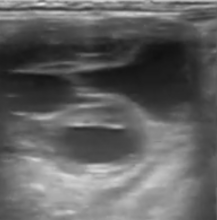

• Ovaires : Suivi de la dynamique folliculaire pour prédire l’ovulation et détecter d'éventuelles anomalies fonctionnelles (corps jaunes persistants, kystes).

• Utérus : Contrôle de la tonicité et de la vacuité utérine. Nous portons une attention particulière à l'absence d'œdème post-ovulatoire excessif ou d'endométrite, facteurs majeurs d'échecs précoces.